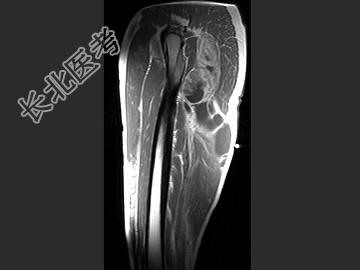

- 单项选择题女,47岁, 足部疼痛,运动员, 结合图像,最可能的诊断是 ( )

A、肌内黏液瘤

B、脂肪瘤

C、血管瘤

D、肌内脓肿

E、滑膜肉瘤